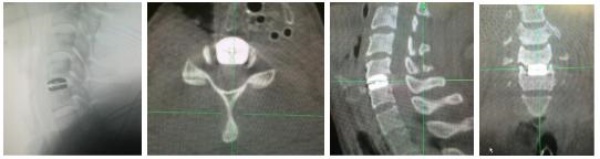

Đặc điểm chẩn đoán hình ảnh: Trên Xquang tầm vận động cột sống cổ (ROM) trung bình tư thế cúi hết cỡ 18.040 ± 7.840 (5 – 350), ngửa hết cỡ 30.000 ± 11.520 (11 – 350). Trên phim MRI có 57.15% thoát vị tại vị trí C5C6, 18.18% thoát vị tại mỗi vị trí C4C5 và C6C7, còn lại 6.49% tại C3C4. Tương ứng với tổn thương trên hình ảnh cộng hưởng từ, chúng tôi tiến hành phẫu thuật thay đĩa đệm nhân tạo cho 59 trường hợp với tổng số 77 đĩa đệm ESP Prosthetic. Thời gian phẫu thuật trung bình 95.28 ± 21.04 phút/1 đĩa, 138.33 ± 34.33 phút/2đĩa và 230.00 ± 42.43 phút/3 đĩa.

Thời gian khám lại trung bình là 37.66 ± 9.28 tháng. 100% bệnh nhân đạt tỷ lệ hồi phục hội chứng tủy cổ tốt và rất tốt. VAS sau khám lại trung bình 1.29 ± 1.69, JOA trung bình 16.13 ± 2.79 điểm, NDI trung bình 7.32 ± 13.63 %, tỷ lệ hồi phục (RR) 87.29 ± 17.90 %. Trên phim Xquang 100% bệnh nhân trên không mất vững cột sống cổ, đĩa đệm nhân tạo đều ở vị trí tốt, không di lệch hay trượt thứ phát, không phát hiện trường hợp nào lún đĩa đệm. Những bệnh nhân sau mổ 6 tháng ROM góc cúi trung bình 27.79 ± 7.940 (trước mổ 17.76 ± 8.220, n = 38), ROM góc ngửa trung bình 45.63 ± 13.280 ( trước mổ 28.55 ± 11.140, n = 38). 3/48 vị trí thay đĩa đệm nhân tạo quá phát xương ở độ I (6.25%), 45/48 vị trí thay đĩa đệm bình thường độ 0 (93.75%) (n=48), tỷ lệ quá phát xương tại vị trí thay đĩa đệm 1.99%/ năm. Tỷ lệ thoái hóa đĩa đệm liền kề là 0.85%/ năm. Mức độ hài lòng của bệnh nhân đạt 97.37%.

Trên phim Xquang sau khám lại, nghiên cứu của chúng tôi 45/48 vị trí thay đĩa đệm bình thường độ 0 (93.75%), tỷ lệ quá phát xương tại vị trí thay đĩa đệm 1.99%/ năm là phù hợp, rất có ý nghĩa vì khi thay đĩa đệm nhân tạo khớp đã được hồi phục dẫn đến tỷ lệ quá phát giảm so với đóng cứng khớp. Trong thời gian theo dõi là 37.66 ± 9.28 tháng, tỷ lệ thoái hóa đĩa đệm liền kề là 0.85%/ năm, tỷ lệ này của chúng tôi là thấp hơn một số tác giả với phương pháp đóng cứng khớp, đây cũng là điều ưu việt khi thay đĩa đệm nhân tạo. S. Litrico và cộng sự nghiên cứu 288 BN phẫu thuật đĩa đệm cột sống cổ có đóng cứng khớp, với thời gian theo dõi 14,5 năm thấy tỷ lệ thoái hóa đĩa đệm liền kề là 5.9%. Reginald J. Davis, MD và cộng sự nghiên cứu 339 BN với thời gian theo dõi 48 tháng cho thấy tỉ lệ thoái hóa đĩa đệm liền kề của nhóm đóng cứng khớp chiếm 6.7% cao hơn nhóm thay đĩa đệm là 2.1% (5 BN), tỷ lệ phải phẫu thuật lại của nhóm thay đĩa đệm là 3.8% (9/234), nhóm đóng cứng khớp là 14.3%. Theo chúng tôi sau khi phẫu thuật thay đĩa đệm, triệu chứng đau cổ của BN được cải thiện nhiều, tầm vận động CSC có biên độ lớn hơn dẫn đến người bệnh sẽ vận động cổ nhiều hơn giúp cho quá trình thoái hóa xương chậm lại [8].